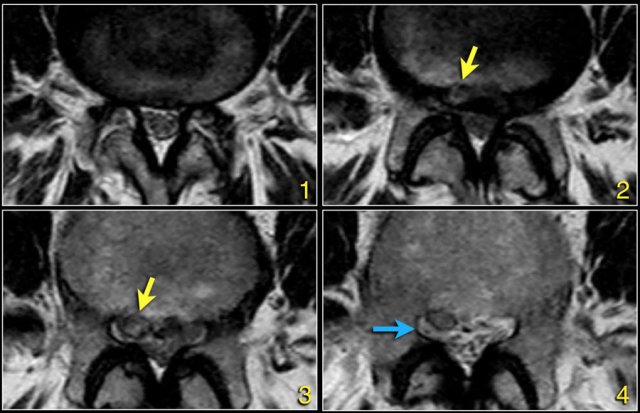

The findings at the different levels 1-4 are:

1. At the level of the disc there is minimal spinal canal narrowing by bulging of the disc and facet arthrosis.

2. At this level there is severe spinal canal stenosis due to bulging disc and facet arthrosis.

There is also an annular tear (high signal) through which the disc herniates (yellow arrow)

3. At the level of the lateral recess, there is a focal herniation of disc material compressing the L5 nerve (yellow arrow).

This is called an extrusion, because the distance between the edges of the disc material is greater than the distance at the base.

4. Compressed L5 nerve (blue arrow) within the lateral recess.

The herniated disc has migrated caudally and is seen as an oval structure anterior to the nerve.

The herniated disc is uncontained, i.e. not covered by fibers of the annulus.